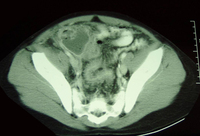

CT scan demonstrating faecalith (white arrow) outside the lumen of the appendix consistent with perforated appendix

From the collection of Dr KuoJen Tsao; used with permission